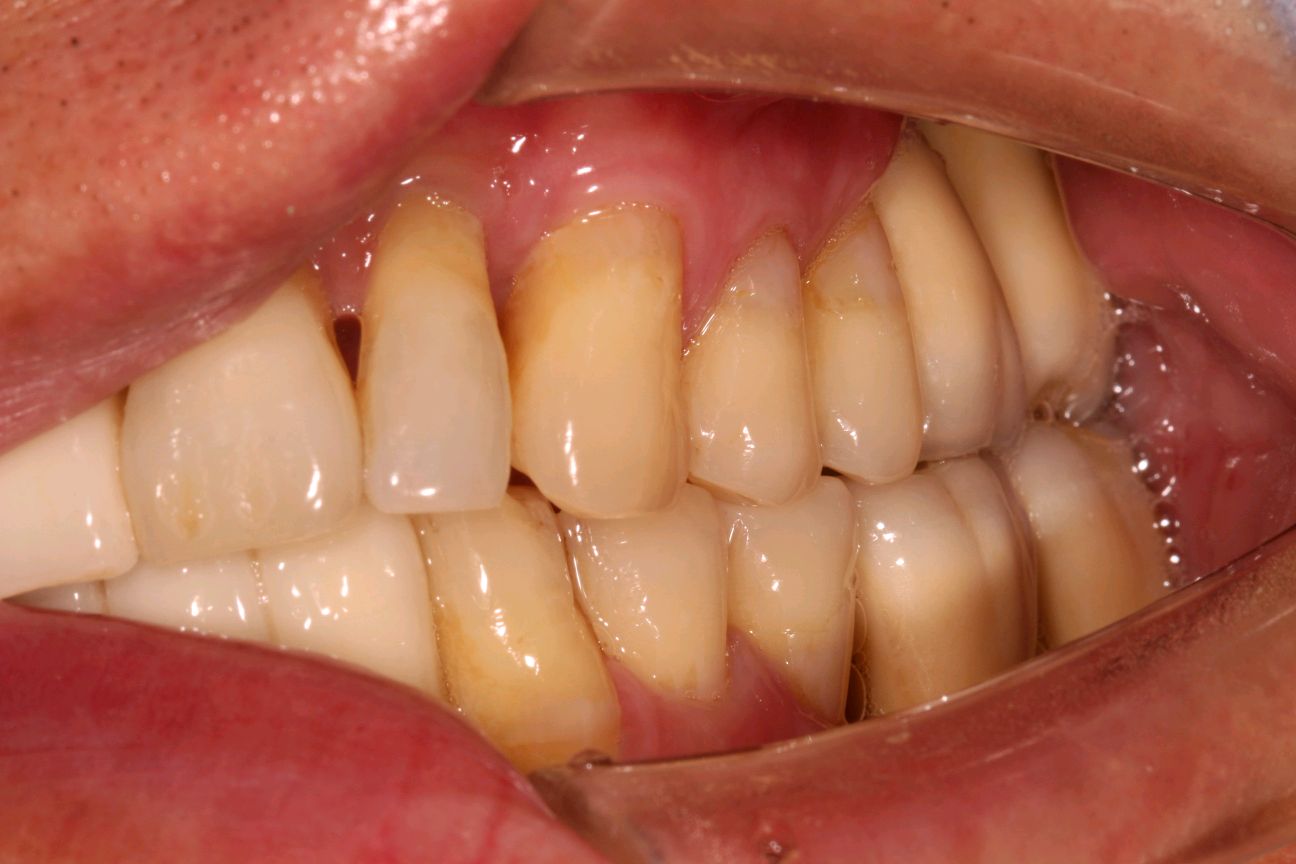

患者要求进行修复,恢复其美观。而种植牙刚好可以满足患者需求。种植牙还可以获得与天然牙功能、结构以及美观十分相似的修复效果。今日如期佩戴牙齿,患者十分满意,重拾自信微笑。

术后修复